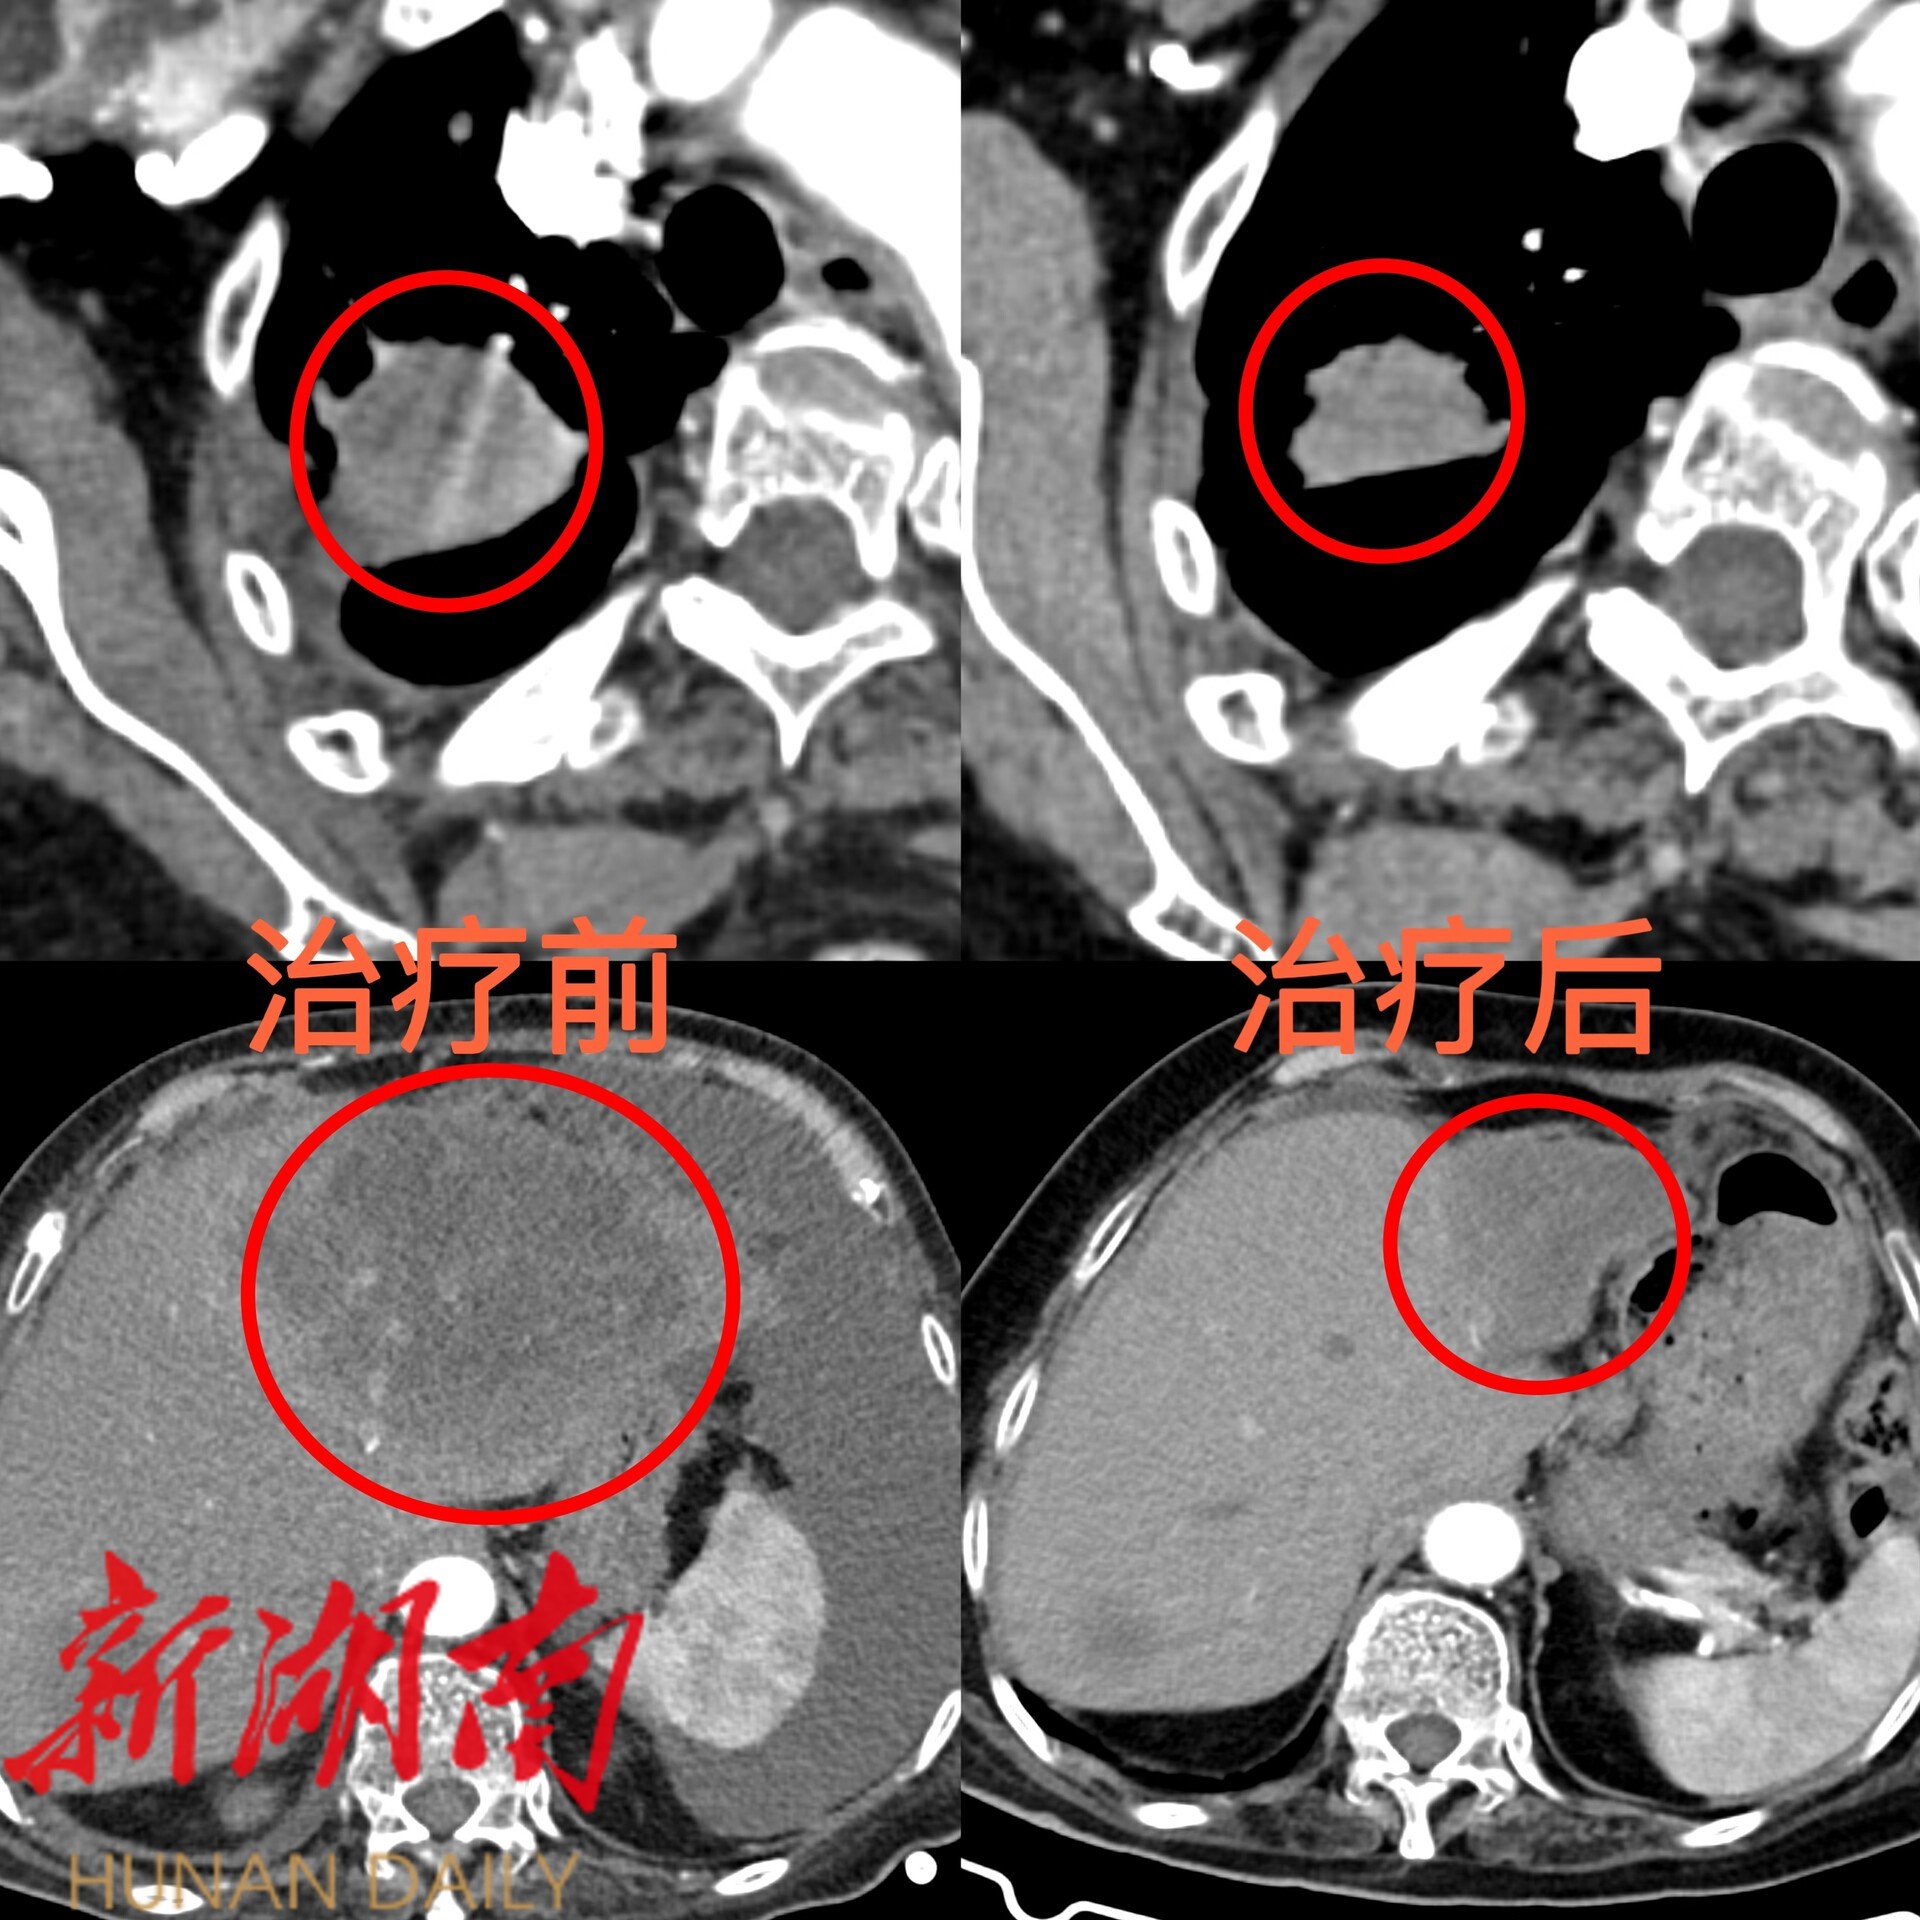

经综合评估,医生为李奶奶选用了口服靶向药。规范服用数月后,今年6月复查结果令人振奋:肺部原发肿瘤和肝脏转移灶均明显缩小,胸腹腔积液完全消失! 曾经折磨李奶奶的胸闷、气促、腹痛等症状显著缓解,生活质量大幅提升。看着检查报告,李奶奶脸上绽放出久违的笑容,向医护人员由衷地竖起了大拇指!